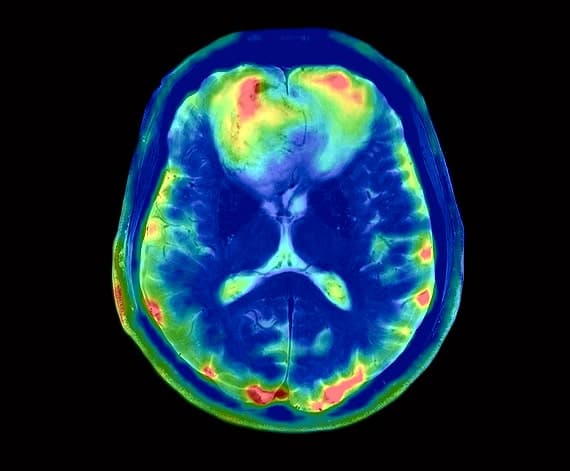

Neuroquant

DTI

Pioneers in Cutting-Edge Imaging for Brain, Neck, Spine Injuries, and Orthopedic Excellence